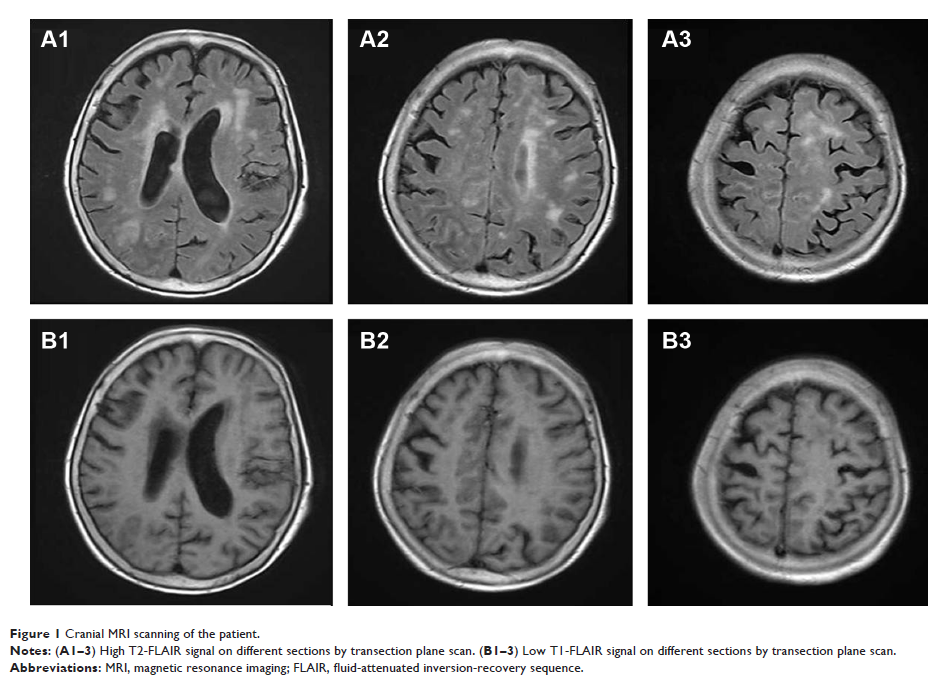

- 作者:Xiaohua Chen, Zhenzhen Xiong, Zhixiong Li, Yali Yang, Zhanying Zheng, Yonghong Li, Yan Xie, Zhe Li

- 期刊:Neuropsychiatric Disease and Treatment